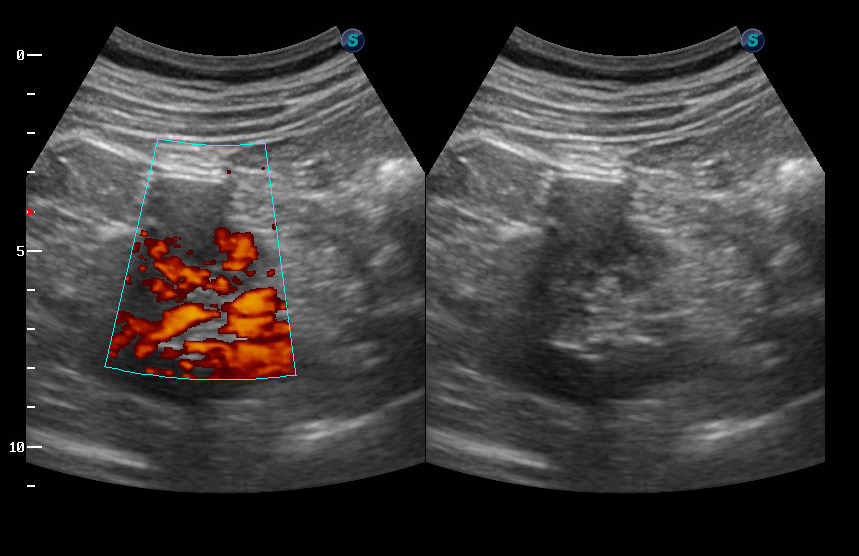

Образование в правой почке

Мужчина средних лет.Жалоб не предъявляет.

С его слов, 10 лет назад в правой почке находили кисту.

гипоэхогенное образование в среднем сегменте, деформирующее контур почки...наверное рак

Ответ каунасских радиологов - киста почки.

В том то и дело. Но тем не менее - это киста, анамнез уже несколько лет.besliu писал(а):Что-то на узи на кисту не похоже...

Кровотока ни грамма- Киста

Динамики нет, на последнем видео четко видна киста при включенной 2й гармонике